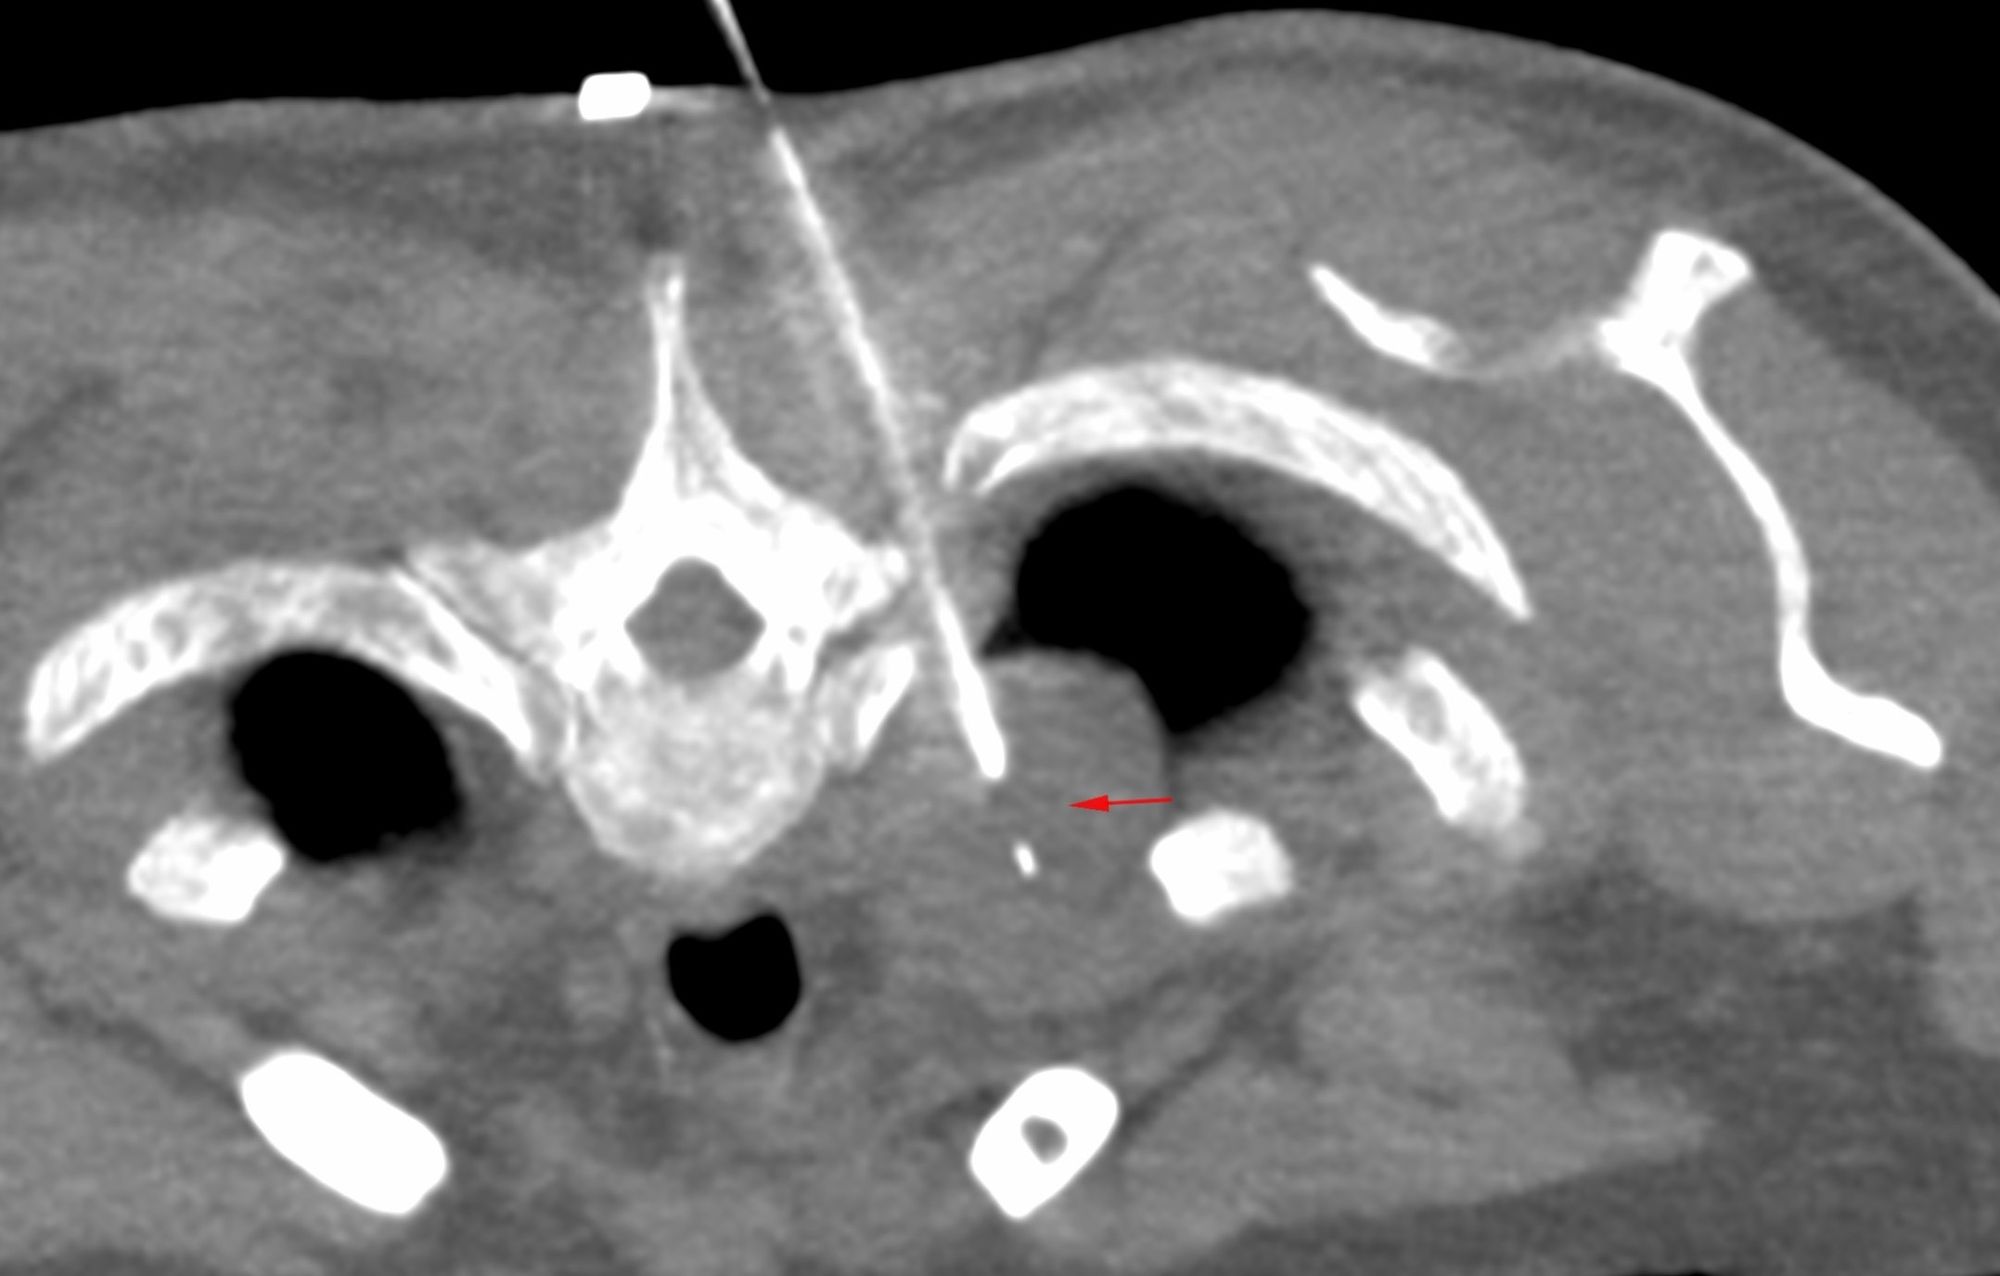

Bone and Soft Tissue Tumors [ペーパーバック] Campanacci, Soft Tissue Tumor - CT Guided Biopsy,

Soft Tissue Tumor - CT Guided Biopsy, em>BCOR‑CCNB3 sarcoma arising in the proximal tibia: A